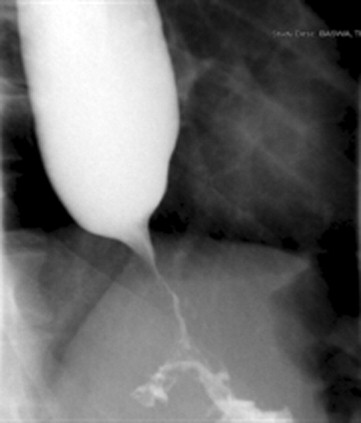

• El examen radiológico a menudo muestra una imagen típica de pico de pájaro en la unión esofagogástrica, con un cuerpo esofágico dilatado. En la acalasia más avanzada, puede ocurrir una dilatación severa con estasis de alimentos.